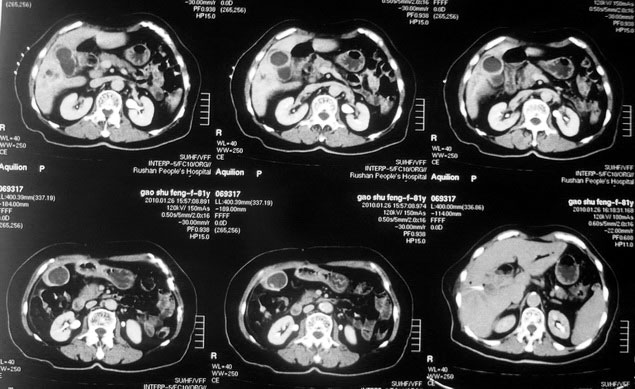

女,80岁既往有胆系手术史。近2月出现食欲不振,近20天出现畏寒发热,体重约下降10kg,体温一般在38℃左右。血常规wbc正常,中性比例88%,cea 10.3,afp、ca199均正常。做过一次肝穿,抽出约3ml仿佛脓性液体。这是她的增强ct扫描,请大家帮帮忙。另外想问问肝脓肿和胆管细胞癌的ct表现有什么区别。谢谢了。

【湘江一滴】化脓性胆囊炎及胆管炎,肝内胆管积气、积液、扩张;胆囊壁增厚、强化;胆周积液。未见肝内占位征象。

【shuiyuan】化脓性胆囊炎及胆管炎,肝内胆管积气、积液、扩张;胆囊壁增厚、强化;胆周积液.

肝脓肿动脉期呈明显环形强化或蜂窝状强化,胆管细胞癌动脉期强化不明显,且伴肝内胆管扩张。

【zenxisengming 】肝内胆管扩张积气,胆囊比环形增厚,胆囊周围渗出,未见占位性病变,应该是胆道化脓性感染

【sunbin】肝内见多个气体密度影伴气液面,胆囊壁增厚,胆囊周围低密度环绕,未见强化,支持化脓性胆管炎、胆囊炎。

最近复查ct,做了第二次穿刺抽脓,顺便做了涂片病理活检,结果找到恶性肿瘤细胞,诊断肝癌合并肝脓肿。看来大家都走眼了啊。